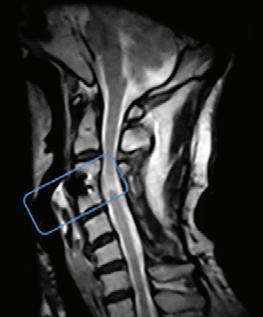

What a weight-bearing MRI reveals vs. a Supine MRI

G-scan Brio Reveals What Supine MRI Misses

Conventional MRI may not demonstrate the pathology related to these symptoms, but G-scan Brio gives you a new point of view so you can accurately diagnose MSK pathologies affected by weight-bearing position.

The G-scan Bro is superior to other MRIs because both the magnet and patient can rotate from 0 to 90 degrees.

G-scan Brio offers a revolutionary MRI approach that increases diagnostic accuracy and confidence for musculoskeletal applications.

G-Scan - Anterolistesis G-Scan - Disc Modification Cervical scan

Supine MRI G-Scan - Anterolistesis G-Scan - Disc Modification Cervical scan More Detail, Better Accuracy,